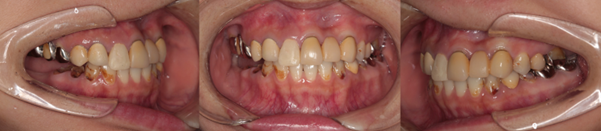

インプラント症例2

Before

インプラント症例2 治療前

After

インプラント症例2 治療後

年齢・性別

30代女性

治療動機

子育てが忙しく、むし歯を長年治すことができなかった。まだ授乳中だけれど、歯がどんどん悪くなるのを自覚して、危機感を持って来院されました。今後は自分の健康を大切にしたいとのことでした。

病歴

右下6、7歯はむし歯のために保存不可能でした。その他にも全顎的に虫歯が多発していました。右下のインプラント以外の治療については コチラ をご参照ください。

治療内容

右下6、7歯の抜歯と骨造成を行い、9カ月待機後インプラントを2本埋入、3カ月待機後チタン+ジルコニア製の上部構造を装着しました。

治療期間

14カ月

治療費概算

約126万円

治療後の状況

見違えるほど見た目が改善されたことを大変喜んでいただきました。患者様は大変モチベーションが高く、口腔内清掃を毎日頑張ってされています。それから1〜3か月ごとのメンテナンスには欠かさず来てくださっています。